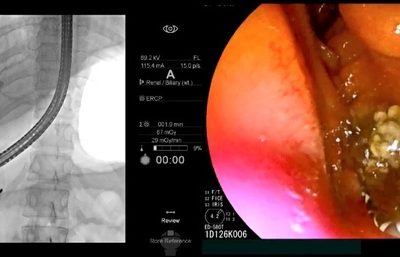

기름진 고기 먹고 배 아파 ‘응급실 행’… 원인은 ‘담관결석’

고령화·서구 식습관 원인… 10년 새 2배 급증 일반적인 복통과 증상 유사 초기 진단 어려워 “기름진 음식·과식 피하고 급격 다이어트 금물” 20대 A씨는 최근 기름진 음식을

삼겹살 먹은 뒤 배 아파서 ‘응급실 행’…10년 새 2배 급증한 ‘이 병’

20대 A씨는 최근 기름진 음식을 먹은 뒤 명치에 심한 통증이 지속돼 병원 응급실을 찾았다. 복부 컴퓨터단층촬영(CT) 등 검사를 받았지만, 별다른 이상은 발견되지 않았고, 몇 시간